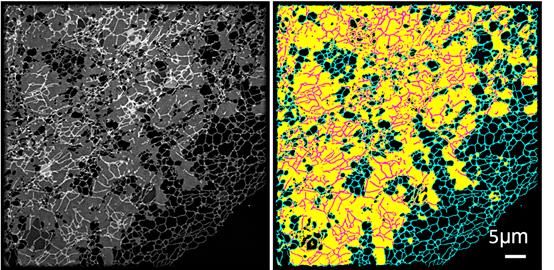

左图:结构光照明成像显示内质网的结构;

右图:ERnet分析图像后标记处不同部分的内质网结构,青色-管状内质网,黄色-片状内质网,紫色-片上管状内质网

本研究则是CIRCE在细胞器和成像研究方面另一重大突破,本次研究重点对象为细胞内质网。“ERnet”基于Transformer的结构搭建而成,被应用于多款其他人工智能模型中。这个超分辨率成像技术与人工智能的融合给生物学研究带来了革命性的影响,借助“ERnet”,研究人员发现了一种新的内质网结构——片上管状内质网,这一发现首次证明了片状和管状内质网在结构上有广泛的交集,更新了科学界对内质网结构、分布和动态的认识,后续能更深入了解其结构与功能紊乱的关系,在科学上具有重要的创新意义。

借助“ERnet”,研究人员还能快速分析不同疾病和健康问题模型中内质网的结构,发现多种类型疾病模型所对应的内质网的结构特征,并给出多参数的量化结果,使得不同条件下的内质网结构能够在统一的分析框架下进行比较,可应用于健康领域产品的功能因子筛选、功效验证和机制可视化研究,具有较高的科研和产品转化应用价值。